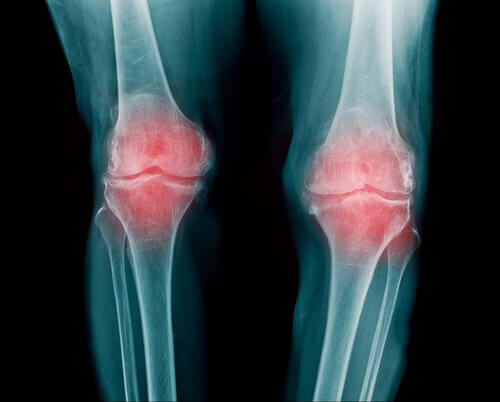

Leddgikt

- Leddgikt, eller revmatoid artritt, er en betennelse i leddet. Det kan påvirke flere ulike ledd. Vanligvis oppstår det i fingre, armer og knær.

- Det starter som regel i en alder av mellom 30 og 60 år, og er vanligst hos kvinner. Det er ingen forskjeller på forekomsten mellom rase eller geografiske plasseringer.

- Personer med leddgikt har redusert mobilitet. Etter prikkingen kommer verre smerte.